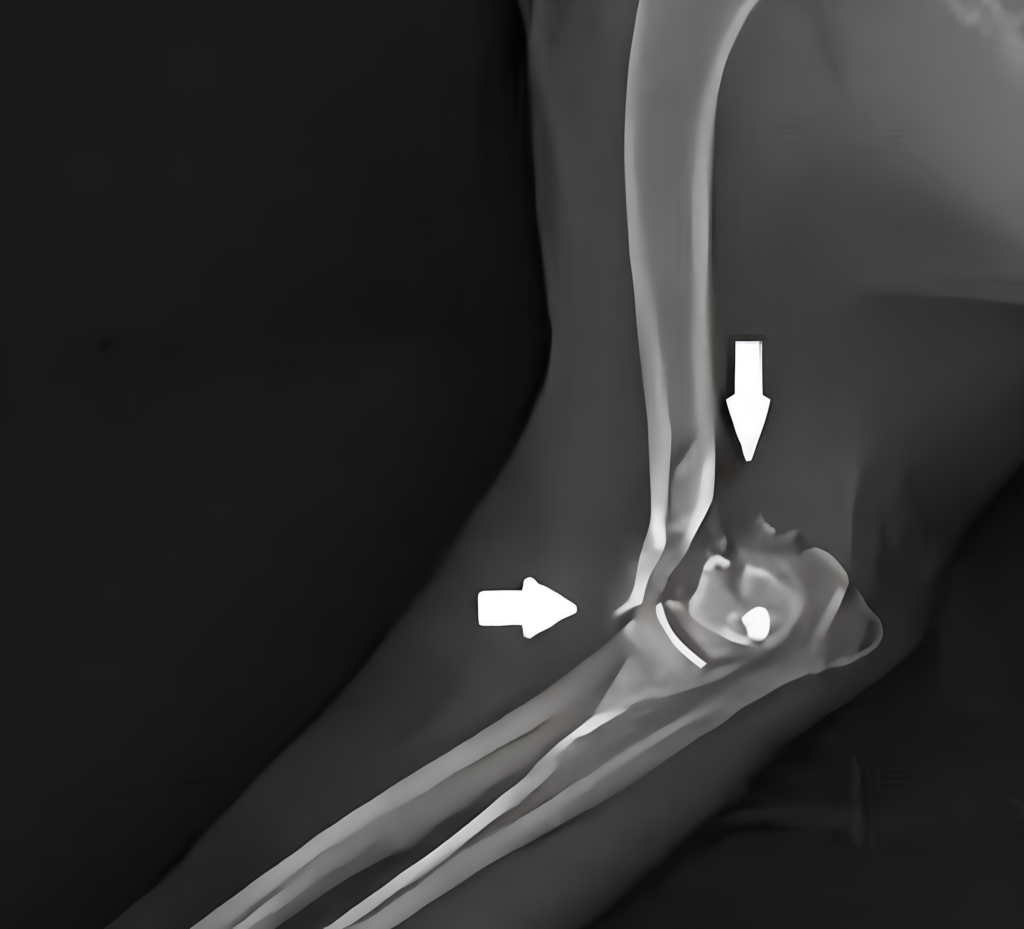

Skipy was immediately taken to Shane Veterinary Hospital for X-rays of his leg. The results revealed a severe humerus fracture, requiring urgent surgery. The repair will be more complicated than most fractures due to its proximity to the growth plate.